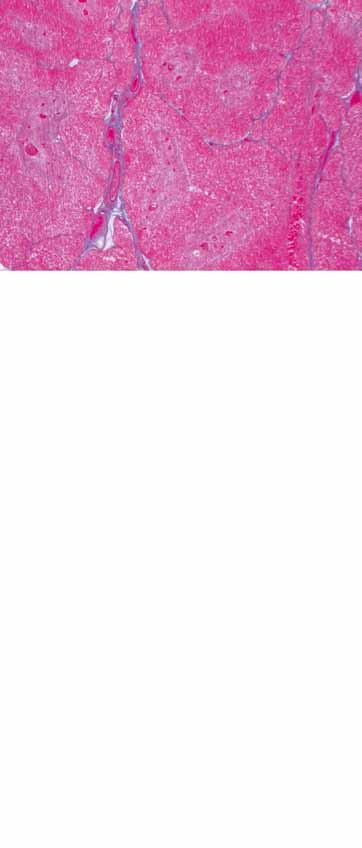

Obr. 1.2 Histologický snímek. Mikroskopická stavba stěny lidské aorty (a) a jedné arterie svalového typu s provázející vénou (b). Na (a) lze rozpoznat trojvrstvou výstavbu stěny aorty s intimou (1), medií (2) a adventicií (3). V poslední jmenované vrstvě se nachází vasa vasorum (4), které zásobuje cévní stěny. Zbarvení obzvlášť dobře ukazuje početná elastická vlákna (5) medie, stejně jako membrana elastica interna (6) a externa (7). Na (b) lze rozpoznat zřetelný rozdíl v tloušťce cévní stěny arterie (8) a vény (9), který lze z velké části přičíst rozdílné tloušťce medie (2). Adventicie cév přechází plynule do okolní pojivové tkáně (10). [L 111]